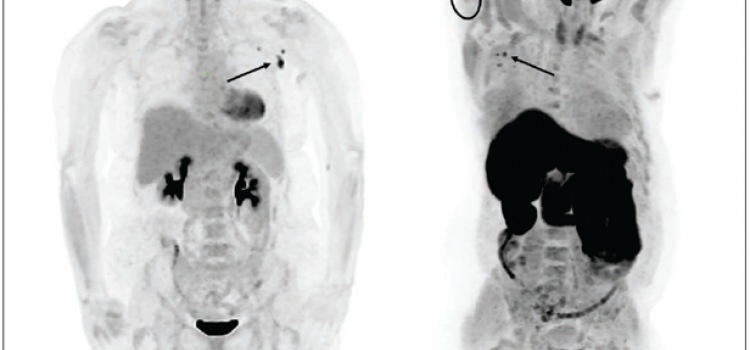

May 19, 2021 — According to an open-access article in ARRS’ American Journal of Roentgenology (AJR), increased axillary ...